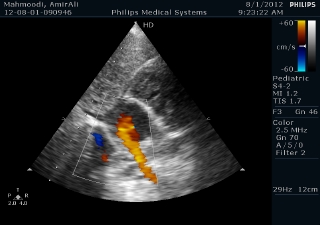

فوق تخصص قلب اطفال

دكتر سعيد مجتهد زاده

دكتر فاطمه وزيري

دكتر شهلا رود پيما